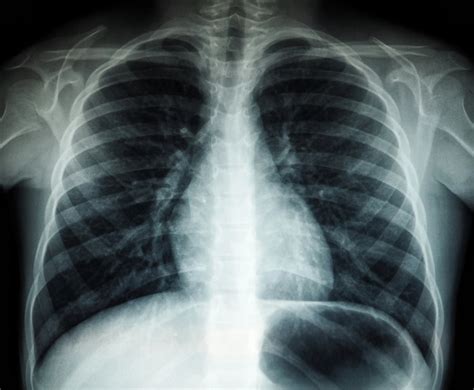

Naujagimio kvėpavimo sutrikimo diagnostika apima fizinį naujagimio ištyrimą, kurio metu vertinami kvėpavimo dažniai, širdies ritmas ir odos spalva. Taip pat gali būti atliekami radiologiniai tyrimai, tokie kaip krūtinės ląstos rentgenograma, siekiant įvertinti plaučių būklę.